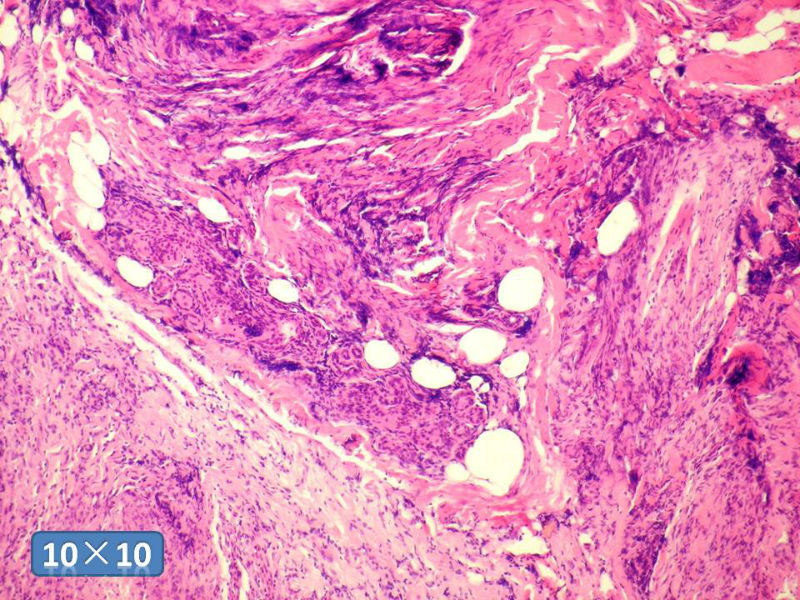

女性,50岁,乳腺肿物,冰冻切片(图1-25)

HE